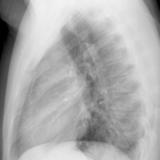

Case 9 Thymoma Lat

Date: 04/04/2010

Views: 3176